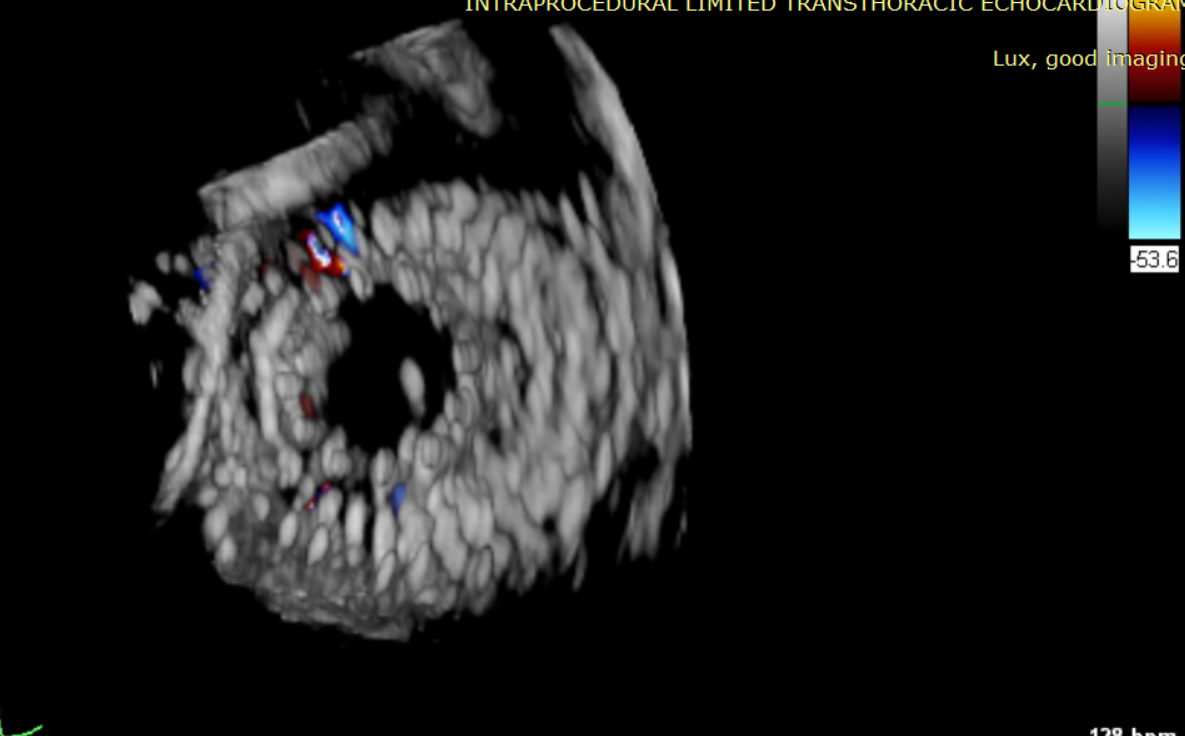

術前超聲提示大量三尖瓣反流

術中輸送器在超聲引導下調整位置

術后超聲提示僅殘余輕微瓣周漏

術后Azeem Latib教授對LuX-Valve Plus經血管三尖瓣置換系統的器械性能和治療效果大為稱贊,并且認為LuX-Valve Plus的手術體驗非常好。從治療效果來看,術后即刻超聲顯示三尖瓣反流幾乎完全消失,血流動力學改善顯著,患者恢復快。在面對復雜解剖結構、超聲影像質量不佳、有起搏導線干擾時,Lux-Valve Plus也體現了極強的適應性。Thomas Modine教授參與了術中指導,他同樣再次肯定了LuX-Valve Plus術中操作的便捷性,認為LuX-Valve Plus容錯率高,對術中影像的依賴小,并表達了后期希望可以更多地應用LuX-Valve Plus三尖瓣置換系統于臨床實踐,讓更多的三尖瓣重度反流患者盡早獲益,改善預后。